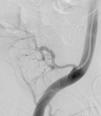

Neste contexto, decidiu-se efetuar angiografia invasiva por acesso arterial femoral direito. Este exame evidenciou fluxo muito escasso na artéria renal do enxerto e imagens hipotransparentes múltiplas e difusas, sugestivas de trombos organizados ao longo de todo o trajeto da artéria renal do rim transplantado (Figura 1). Procedeu-se a canulação seletiva com cateter de mamária interna e introdução na artéria renal de fio guia Balance Middleweight Universal II 0,14” (Abbott vascular®). De seguida, utilizando o sistema de aspiração por cateter Pronto V3 6F (vascular solutions, Inc.®), procedeu-se à aspiração de conteúdo intra-arterial, confirmando-se macroscopicamente a existência de material com aspecto trombótico (Figuras 2–4). Posteriormente, efetuou-se angioplastia com balão em toda a extensão da artéria renal (Figura 5). A melhoria angiográfica foi imediata, com visualização da sombra renal, evidenciando-se, no entanto, discretas irregularidades parietais (Figura 6). A terapêutica farmacológica adjuvante instituída consistiu em ácido acetilsalicílico (100mg/d), heparina não fracionada (5000U/bólus seguida de 100 U/kg/h) durante 72h e, subsequentemente, hipocoagulação oral com varfarina (INR alvo 2,0-3,0).